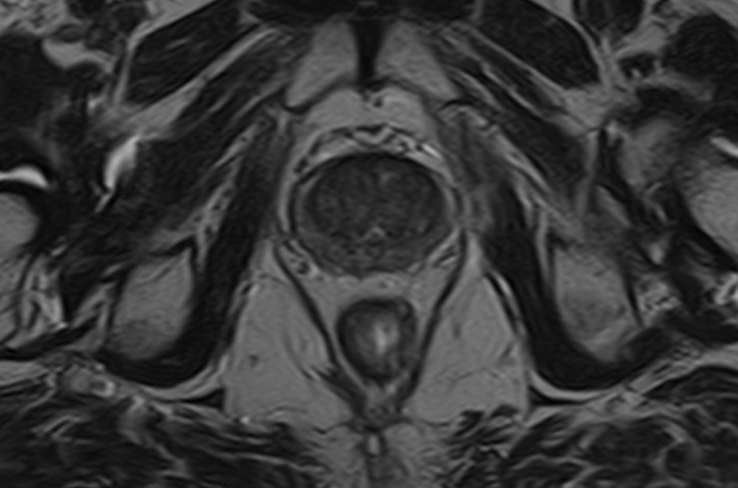

Магнитно-резонансная томография органов малого таза у мужчин подразумевает послойное сканирование анатомической зоны предстательной железы, мочевого пузыря с мочеточниками, прямой кишки и полости малого таза с окружающими мягкими тканями.

структуру предстательной железы, а также выявить происходящее в ней патологические процессы. К примеру, для таких заболеваний, как простатит, аденома простаты (доброкачественная гиперплазия) и рак простаты очень важна ранняя диагностика, что и позволяет МРТ. Для обследования простаты метод МРТ является уникальным по своей информативности.

Кроме предстательной железы при исследовании визуализируются семенные пузырьки, семявыводящие протоки.